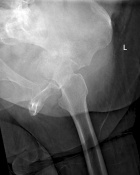

63 year old female complains of increasing left hip pain after a fall three weeks ago

History of breast cancer